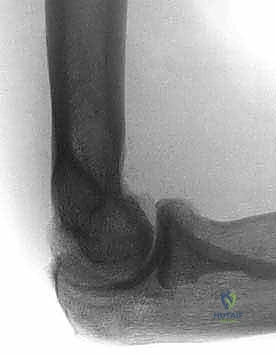

- الأشعة السينية (X-rays): لتقييم شكل العظام، البحث عن الكسور القديمة، وتحديد أماكن النتوءات العظمية والأجسام الحرة الكبيرة.

- الأشعة المقطعية ثلاثية الأبعاد (3D CT Scan): وهي الأهم قبل الجراحة. تعطي الجراح خريطة مجسمة دقيقة لكل نتوء عظمي وكل حاجز ميكانيكي داخل المفصل، مما يسهل استهدافه بالمنظار.